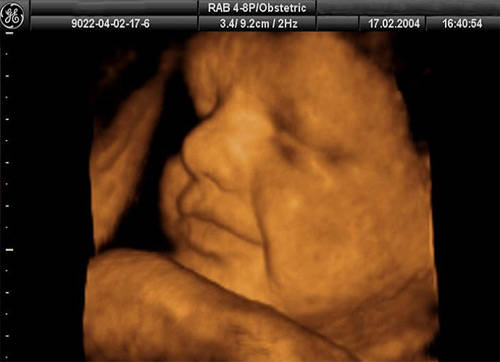

| 36 haftalık gebelik, bir hamilelik sürecinin önemli bir aşamasını temsil eder. Bu dönem, fetüsün gelişiminde kritik bir dönemdir ve anne adayının sağlığı bakımından da dikkate alınması gereken birçok faktör vardır. Bu makalede, 36 haftalık gebelik sürecinin özellikleri, anne adayı ve fetüs üzerindeki etkileri ile birlikte, bu dönemde dikkat edilmesi gereken konular ele alınacaktır. Fetüs Gelişimi 36 haftalık gebelikte fetüs, doğuma oldukça yakın bir dönemde bulunmaktadır. Bu aşamada fetüsün gelişimi ile ilgili bazı önemli noktalar şunlardır:

36 haftalık gebelik sürecinde yaşadıklarım gerçekten çok ilginç. Bebeğimin boyunun 47 cm ve ağırlığının 2 kg 700 gram olması beni heyecanlandırıyor. Her gün ortalama 30 gram alması da bu süreçteki gelişimini gösteriyor. Bebeğin doğuma hazırlandığını bilmek güzel ama bu haftayı atlatmanın verdiği rahatlıkla birlikte üzerimdeki yükün biraz hafiflemesi de sevindirici. Hormonal değişimler nedeniyle bedenimdeki gevşeme ve yumuşama beni yavaşlatıyor. Yürüyüşlerim değişti, bu da normal. Ancak bel ve pelvisteki ağrılar beni rahatsız ediyor. Yemek yeme konusunda da sıkıntılar yaşıyorum, bebeğim artık çok yer kaplıyor. Küçük porsiyonlarla beslenmek zorundayım. Mide yanmamın hafiflemesi, nefes almamı kolaylaştırdı ama bebeğim aşağı doğru inmeye çalıştıkça alt karın bölgesinde baskı hissediyorum, bu da rahatsız edici. Braxton Hicks kasılmalarının daha fazla hissedilmesi de dikkatimi çekiyor. Doğum sancılarının başlaması için her an hazırlıklı olmam gerektiğini biliyorum. Bebeğimin hareketlerinde azalma olursa ya da vajinal kanama yaşarsam hemen doktora gitmem gerektiğini unutmayacağım. Vajinal akıntıdaki artış beni endişelendiriyor ama cinsel birliktelikten sonra lekelenmenin normal olduğunu öğrenmek biraz olsun rahatlatıyor. Karın kaşıntım da dayanılmaz hale geldi; badem yağı ve E vitamini kremleri kullanmaya başladım. Uyku sorunlarıyla başa çıkmak için rahat kıyafetler giymek zorundayım. Ayaklarımda ve bileklerimdeki şişlik beni oldukça rahatsız ediyor fakat bol sıvı tüketmeye dikkat ediyorum. Halsizlik hissi normal ama doğumun yaklaşmasıyla birlikte bir enerji patlaması yaşıyorum. Artık tuvalet ihtiyacım da arttı, bu durum da yeni bir alışkanlık haline geldi. Tüm bu süreç gerçekten hem zorlu hem de heyecan verici!